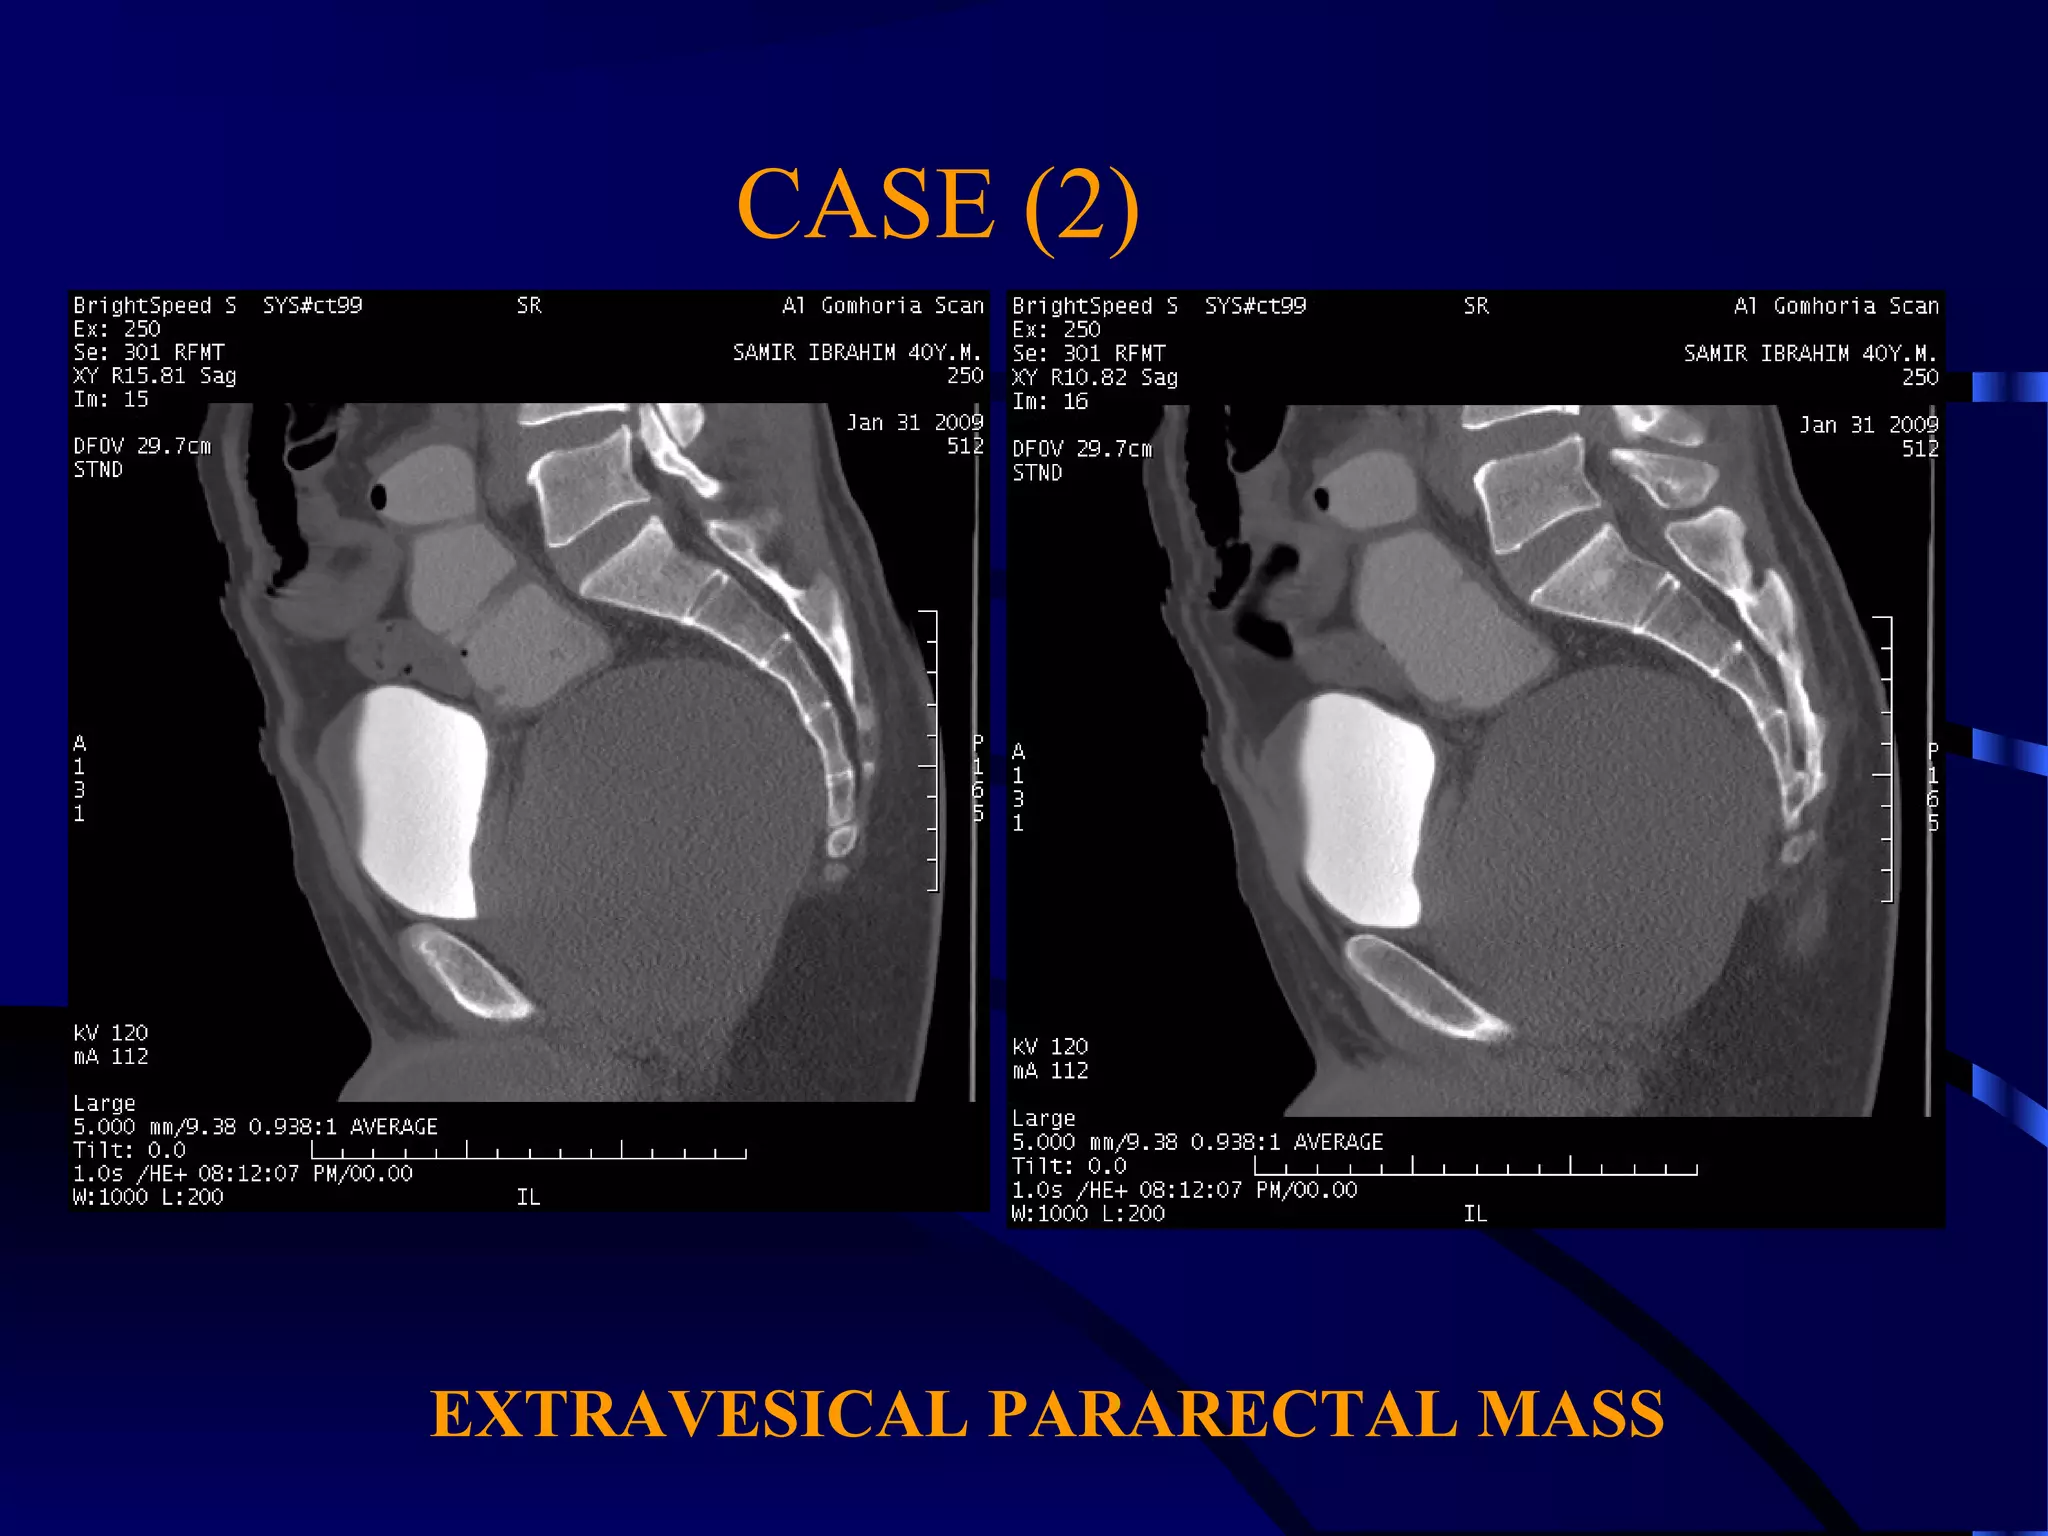

CASE (2)

EXTRAVESICAL PARARECTAL MASS